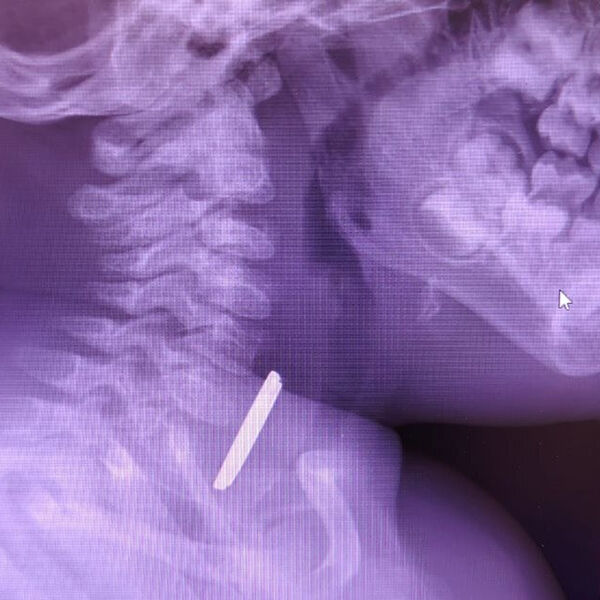

Маленький пациент поступил в больницу с затрудненным глотанием и слюноотделением. Ребенка направили на рентген, который показал наличие батарейки в верхней трети пищевода. Пациента направили направили на экстренную операцию, и под наркозом извлекли предмет, который уже успел причинить здоровью младенца вред.

«Батарейка повредила стенку пищевода, вызвав глубокий электрохимический ожог, занимающий половину просвета пищевода. Учитывая тяжесть состояния от полученной травмы, ребенок был госпитализирован в отделение реанимации, где проводилась интенсивная терапия», — рассказал детский хирург детской больницы Вячеслав Воронин.